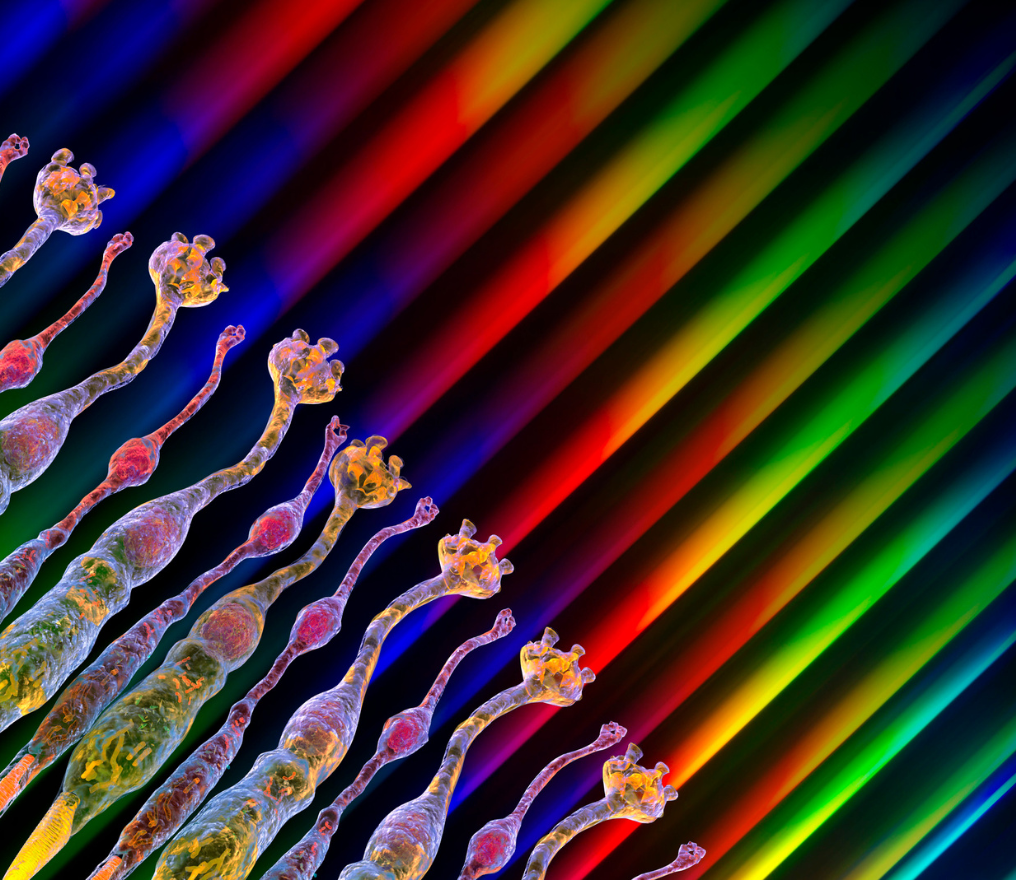

Photorécepteurs : les nouvelles pistes pour préserver la vision

Des rétines artificielles à la thérapie sonogénétique, les pistes des chercheurs pour redonner la vue aux aveugles

Entendre grâce à la lumière